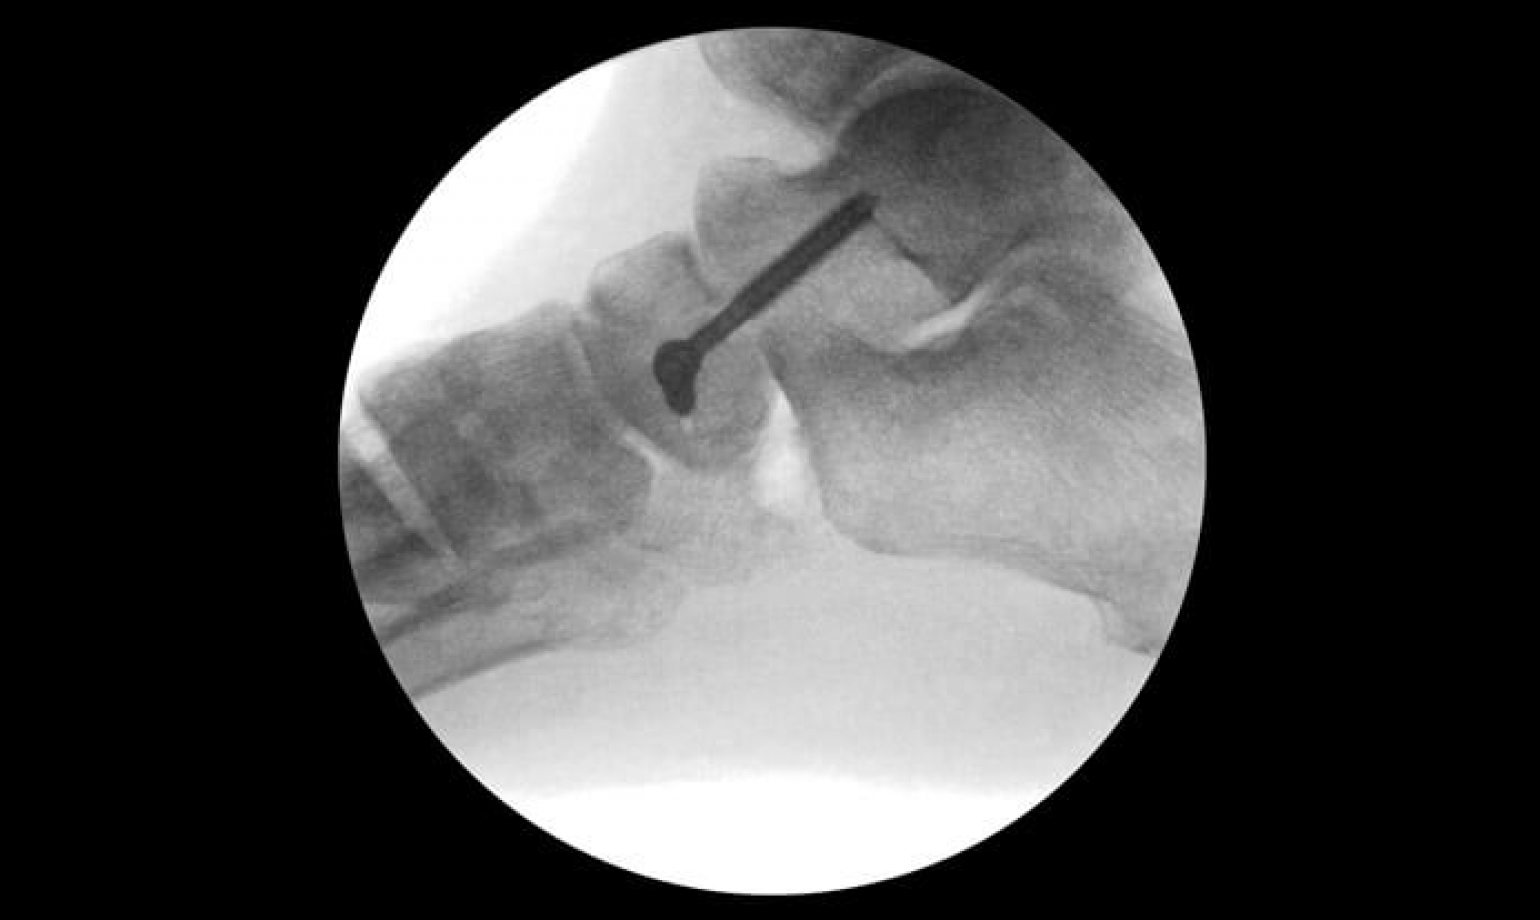

Radiographs of a specimen fixed with an IP Fusion device (Extremity Extremity Medical Hammerfix the extremity medical hammertoe device is indicated for the fixation of osteotomies and reconstruction of the lesser toes following. hammerfix | extremity medical. Allows simultaneous use of intramedullary pin for fixation of mtd joint when necessary. Extremity medical are developing next generation products to address the challenging needs. The extremity medical hammer toe device is indicated for the. Extremity Medical Hammerfix.